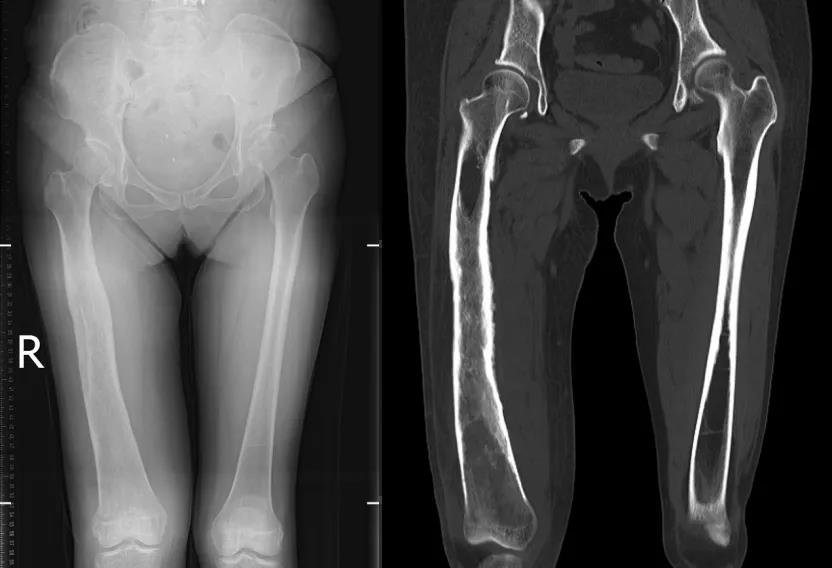

二十年前,宁女士曾因右股骨远端骨髓炎接受手术,术后感染一度得到控制。然而,慢性骨髓炎如同一颗深埋体内的“定时炸弹”,在沉寂多年后悄然复发。近一个月来,她右膝持续肿痛、活动受限,经门诊检查发现大量关节积液,影像学提示右侧股骨远端骨质破坏、骨皮质变薄、骨髓水肿,高度怀疑为骨髓炎复发并继发化脓性关节炎。更令人揪心的是,穿刺培养明确病原体为“金黄色葡萄球菌”——一种常见却极具破坏力的致病菌。

术前DR及CT重建

术前膝关节MRI和股骨MRI